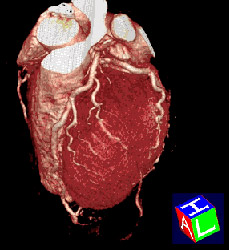

| 心臓を横から見た画像 | 心臓を真正面から見た画像 |

その結果、単に画像が速く綺麗に撮れるということにとどまらず、従来はできなかった縦方向の画像(実際に撮影しているのではなく、検査後にコンピュータで計算させて

上下方向の画像を作成するもの:MPR画像という)や、立体的な3次元画像なども従来よりもはるかに有用なものとして活用できるようになっております。